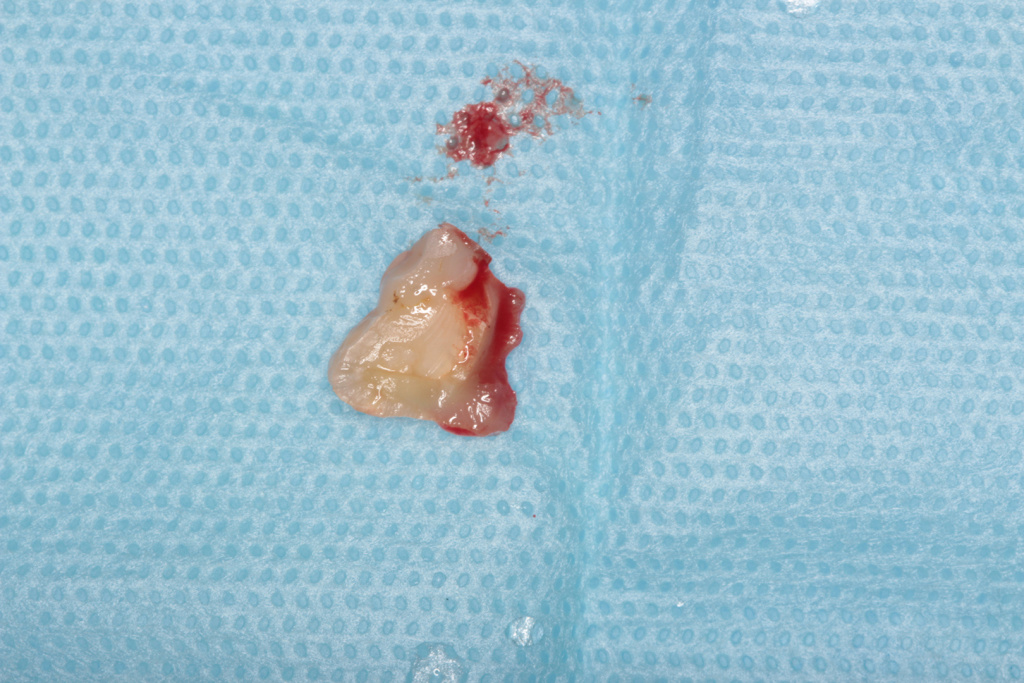

Удаление зуба 3.6